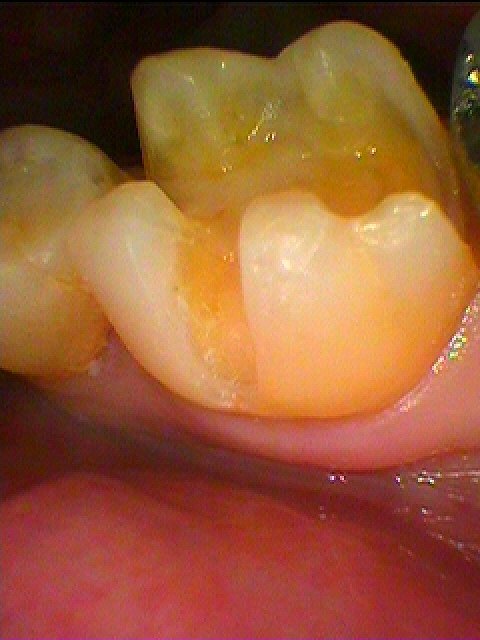

近心部にも虫歯になっています

虫歯が出てきました